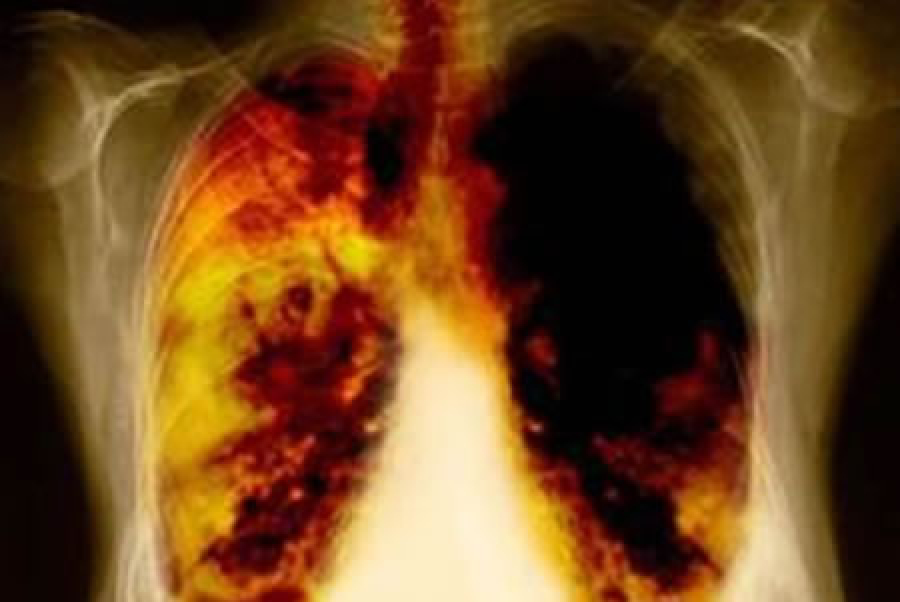

Hasta la fecha, a este grupo de pacientes que no eran candidatos a cirugía se les ofrecía tratamiento con quimio-radioterapia basada en platino, sin embargo, solo 15% alcanzaba supervivencia a 5 años, y aproximadamente 89% presentarían progresión de la enfermedad hacia un estadio metastásico[2].

Durante los resultados más recientes del estudio CASPIAN, durvalumab demostró su eficacia en el control de la progresión de la enfermedad, extendiendo el periodo libre de progresión por 11.2 meses, ya que los pacientes que recibieron este tratamiento alcanzaron 17.2 meses de supervivencia libre de progresión, mientras que los pacientes que únicamente recibían quimio-radioterapia alcanzaron 5.6 meses. Durvalumab fue aprobado en México para los pacientes que han sido diagnosticados con cáncer de pulmón de células no pequeñas, localmente avanzado irresecable, cuya enfermedad no ha progresado después de la terapia de quimiorradiación con base en platino.

Por otro lado, AstraZeneca presentó resultados del estudio ADAURA, en el cual se concluyó que incluir osimertinib a pacientes con cáncer de pulmón, reduce el riesgo de que el tumor vuelva a crecer o de fallecimiento en un 79%[3]. Osimertinib se dirige a una mutación genética específica, sus efectos secundarios son lo suficientemente manejables para usarse durante varios años y así ayudar a prevenir la recurrencia[4]. Dos años después de la cirugía, el 89% de los participantes del estudio se habían librado de una recaída, en comparación con solo el 53% en un grupo con placebo.